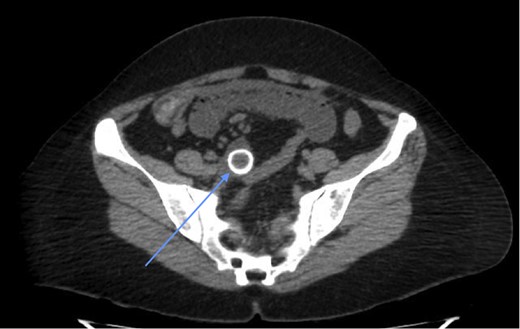

Laboratory investigations (biochemical profile and urinalysis) were all within normal limits. Abdominal CT showed pneumobilia and a 2 cm intraluminal density in the distal ileum with resultant small bowel obstruction (Figs 1 and 2). She underwent emergency laparotomy and enterolithotomy followed by a smooth postoperative course (Figs 3 and 4). The CT scan taken elsewhere and just prior to the emergency cholecystecomy 12 months earlier was reviewed; this demonstrated a markedly distended gallbladder with irregular wall thickening and severe pericholecystic fat stranding consistent with a gallbladder empyema measuring 16 cm × 9.0 cm. There were also multiple gallstones with the largest two measuring 2 cm at the neck of the gallbladder and the other, 2.0 cm in diameter at the fundus of the gallbladder, respectively. There was a narrower, septum-like area between the neck and grossly distended empyema (Fig. 5)

Gallstone after delivery by enterolithotomy. The gallstone measured 2 cm in diameter.